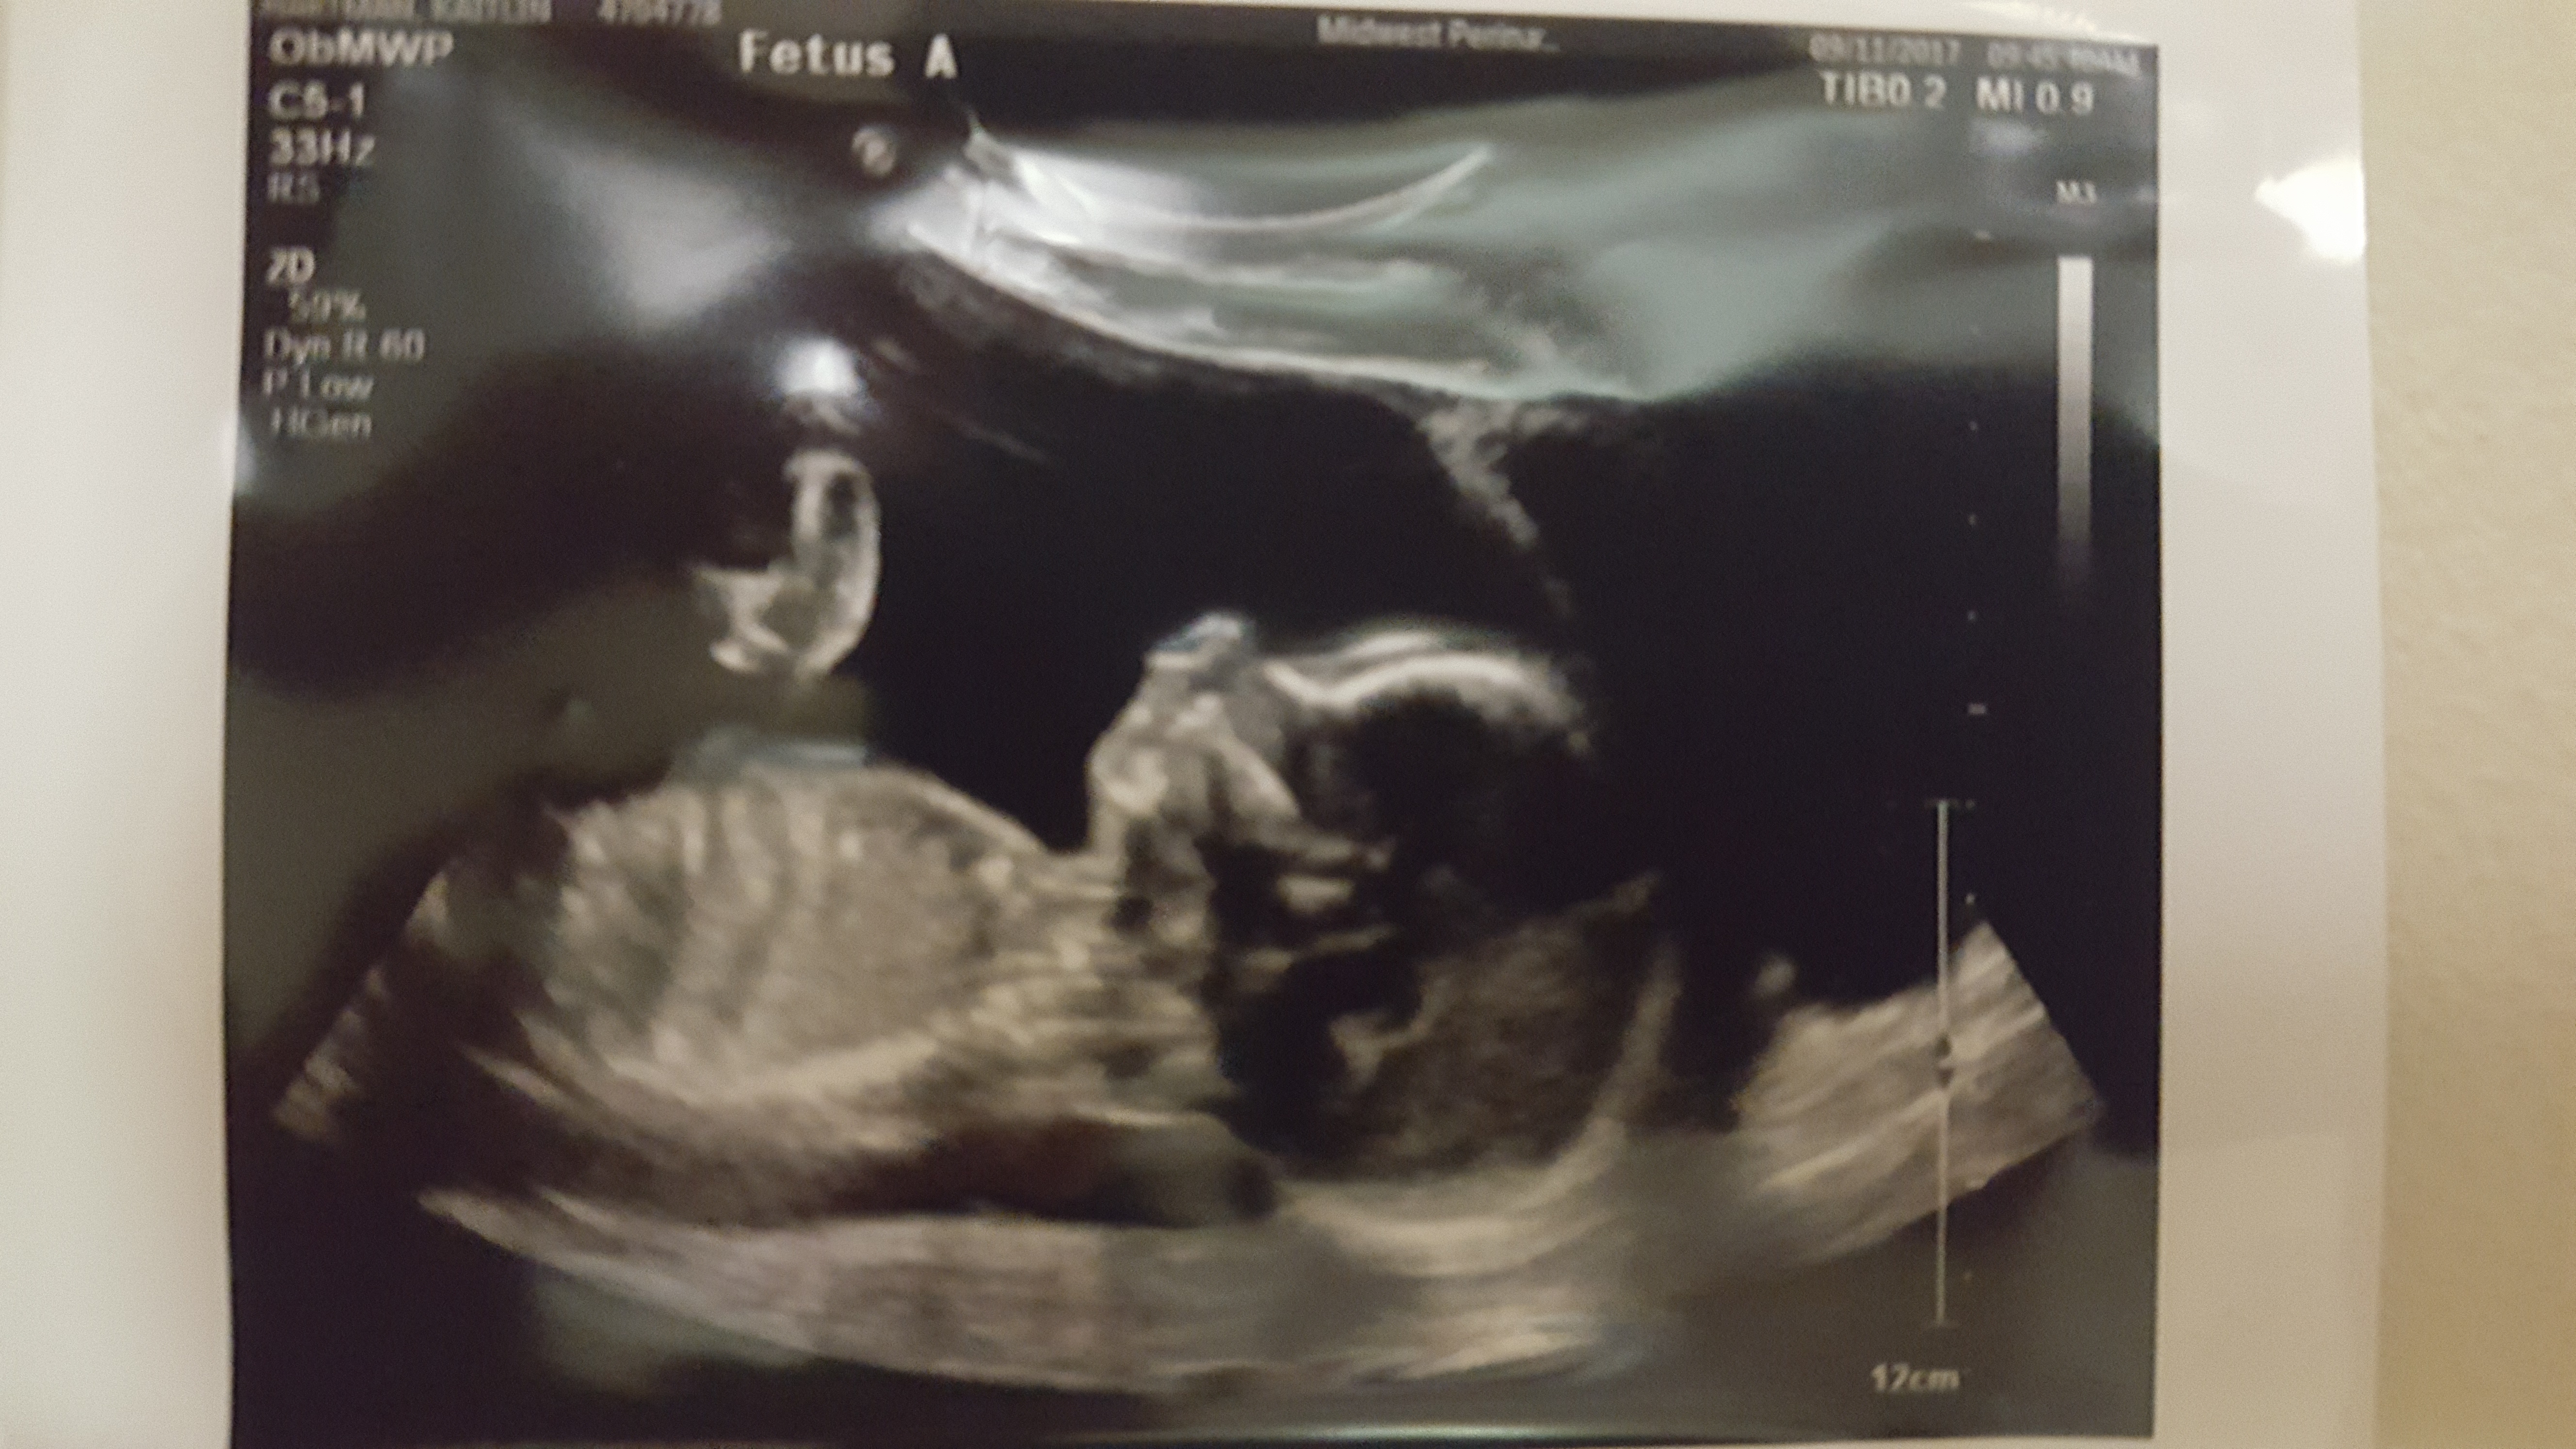

We cannot thank God enough that these 4 little miracles are 21 weeks now!! We get to see them every day and they are each weighing between 8 and 12 oz.  We will continue to be here at the hospital until their “birth” day which we are praying will be at least 7 more weeks. It has definitely been a roller coaster of emotions this week, but most importantly right now Josh and I are thanking God for every day! I don’t think I have ever realized how precious and how much each day is truly a blessing! We know this is just another part of the journey and how beautiful it is to see God’s faithfulness in each day! During this week, Matthew 6:34 has definitely been our verse we keep reflecting on.